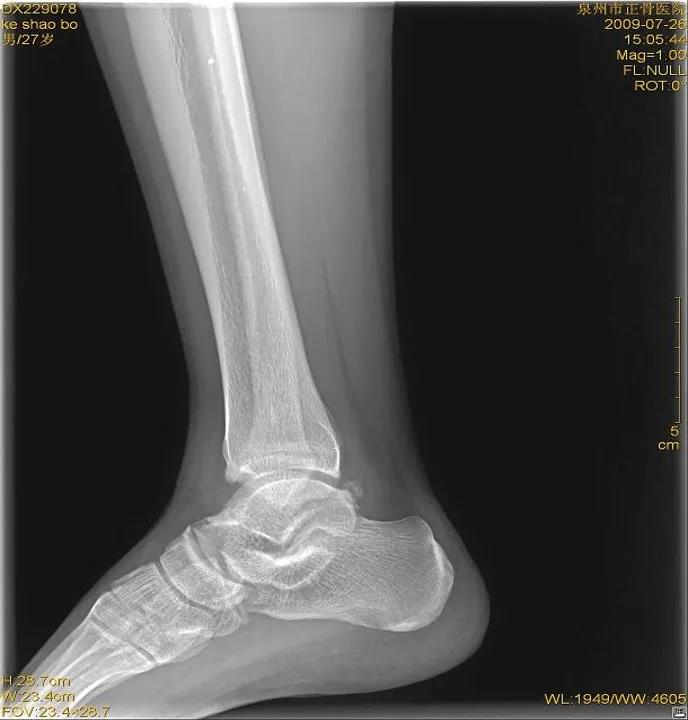

X线

踝关节正位

踝关节侧位

虽然有所防备,但有时难免发生意外。这时,患者可以先自行评估是否出现关节畸形移位或形成假关节(骨头断裂)等,如果遇到这类严重情况应固定后立即就医,如果只是局部的肿胀瘀斑,疼痛程度较低,就可以先自我急救。伤者在进行急救处理后,如有条件最好在医院进行X线或CT检查,因为小骨头的断裂或撕裂等问题并不会引起强烈的疼痛或肿胀等,但如果没有有效的医疗支具固定可能会致骨折错位或损伤进一步加剧,后期恢复不充分,还会导致陈旧性软组织受伤,在关节尤其负重部位容易引发骨关节病等慢性疾病。

X线片:基本的辅助检查(应注意某些情况并非骨折)CT:能进一步检查隐匿性骨折或撕脱性骨折MRI:可检查肌腱、韧带的损伤肌骨超声:可代替或结合MRI检查软组织的损伤